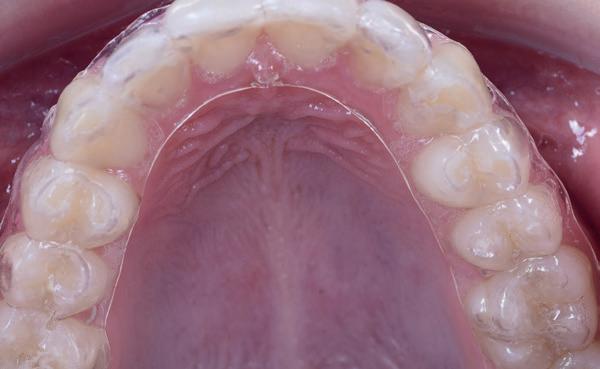

Toekomstige AI-ondersteunde software zal vermoedelijk nog beter risico’s voorspellen op basis van slijtagepatronen, speekselanalyse en leefstijlfactoren. Echter, wanneer er geen scanner in de praktijk beschikbaar is dan is een handige tool het vragen of iemand elke periodieke afspraak zijn retainer meeneemt ter controle. Ontstaan daar slijtfacetten in dan weet je dat iemand s nachts actief is en zul je over moeten gaan op een night guard zoals in het voorbeeld van afbeelding 7-10). Wanneer verwijs je door?